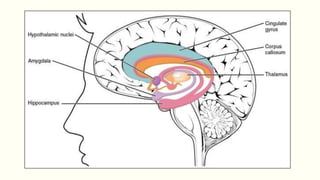

Papez Circuit

Control of emotional expression

Memory storage

Hippocampus

Mammillary

bodies

Mammillothalamic

tract

Anterior

Thalamic Nuclei

Cingulate Gyrus

Parahippocampal

gyrus